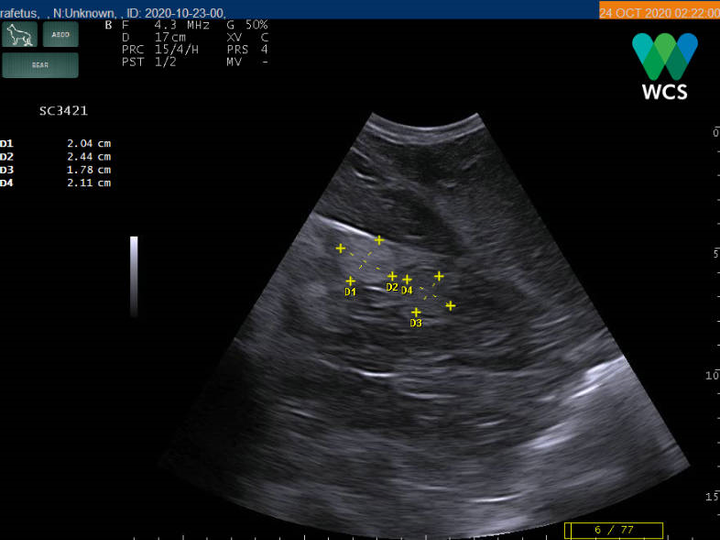

Các nhà khoa học cũng dùng máy siêu âm do các chuyên gia của Hiệp hội Bảo tồn động vật hoang dã (WCS) thực hiện để xác định giới tính và cho ra kết quả giống cái.

Máy siêu âm soi được nang trứng của rùa, khẳng định đây là con rùa cái. (Ảnh: WCS Việt Nam)